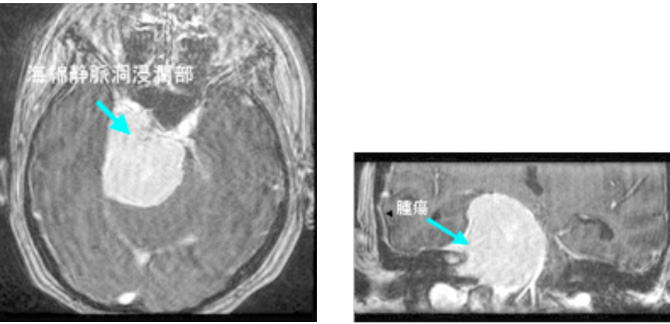

症例2は巨大斜台髄膜腫の症例です。歩行障害・嚥下困難などの症状をもち来院されましたが、腫瘍の大半を切除し、歩いて帰宅することが出来ました。海綿静脈洞部分の腫瘍は取ると合併症が出現するため、この部分は意図的に残しガンマナイフ治療を計画しています。

図2 頭蓋底髄膜腫 48歳女性 歩行障害、嚥下困難で来院

術後MRI:海綿静脈洞への浸潤部を除き

摘出、歩行障害改善し退院